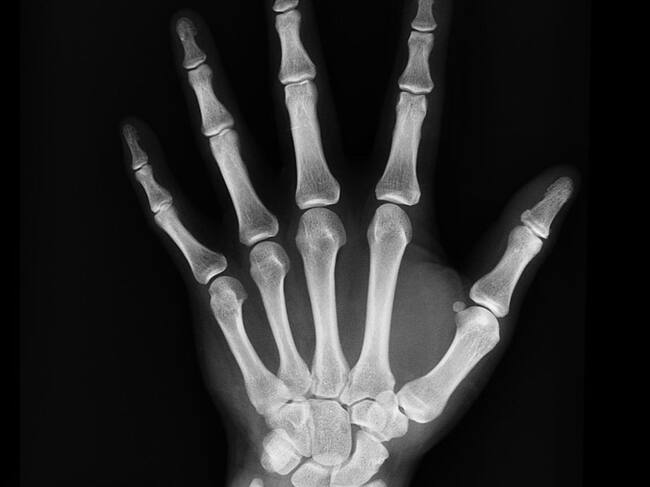

Radiografía de la mano de una persona afectada por hipofosfatasia / UGR

La hipofosfatasia en adultos conlleva una pérdida de mineralización que da lugar a fracturas recurrentes, fracturas femorales, antecedentes de raquitismo y dolor musculoesquelético, además de afecciones dentales. En el caso de los niños es mucho más grave, provocando incluso la muerte prematura a los pocos días de vida, daños cerebrales y problemas respiratorios.